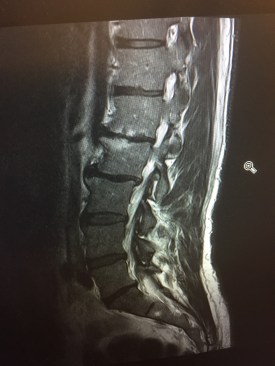

Mijn houding was sowieso al waardeloos. Op enig moment betaal je daar een prijs voor. Dit voetbalseizoen zit erop. De arts in het Groene Hart Ziekenhuis laat de foto’s zien. Diagnose: versleten rug. Drie beschadigde tussenwervels in de onderrug.